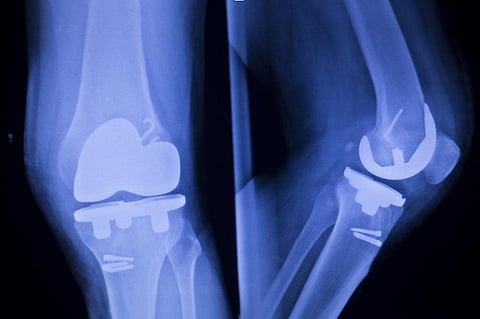

Orthopaedic implants can substitute or repair different tissues, such as bone, cartilage, ligaments and tendons, but they also increase the risk of microbial infections by forming biofilms. Such clusters of bacteria can be highly resistant to antibiotics and, in many cases, implants may have to be surgically removed. Implants made with antimicrobial material can help address this problem.